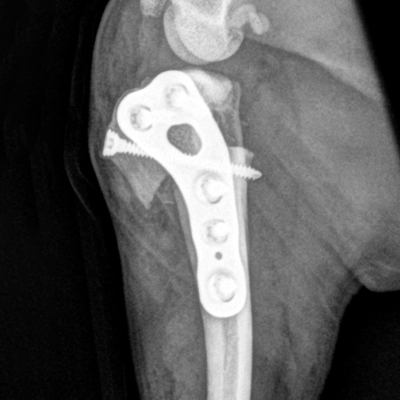

Dr. Toshi Ikeda shared his LeiLOX CBLO case with us: 1 year old Labrador, spayed, female, 30 kg. Our lightweight titanium CBLO Plate features double compression holes, limited contact to bone, and is anatomically contoured.

Thank you, Dr. Ikeda!